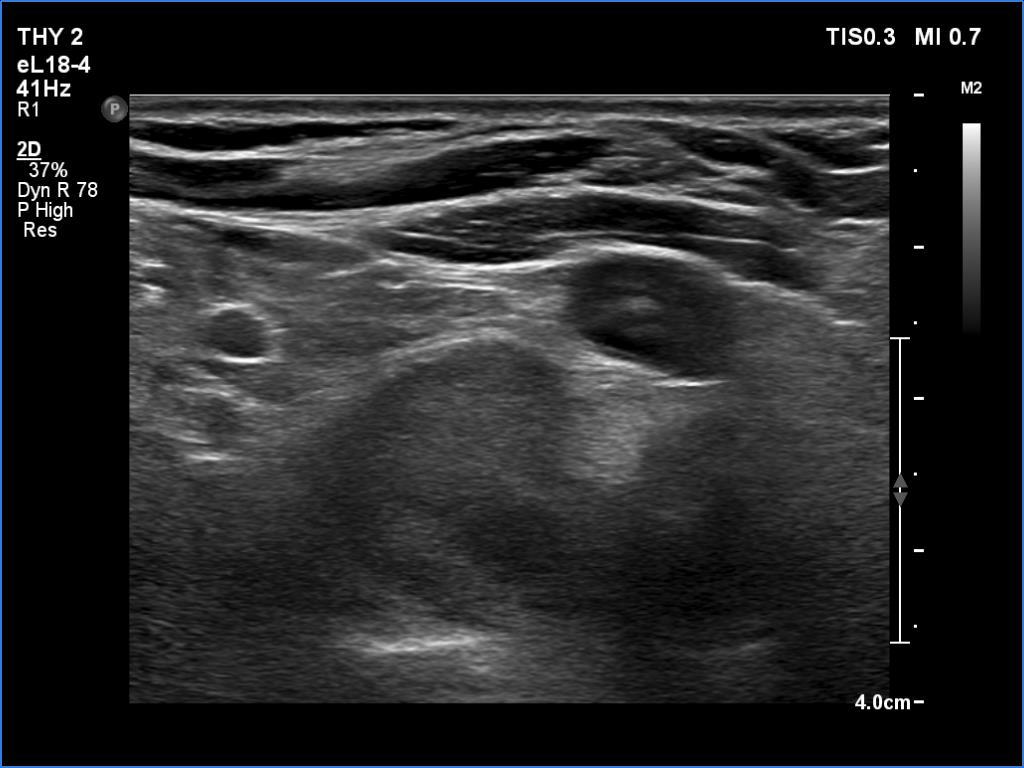

Second examination 6 month later (2nd row of images)

Ultrasonography revealed a hypoechoic mass corresponding to the right lower parathyroid.

If we compare the first and second ultrasound examination, it is evident that the ultrasound examination was not performed according to the rules of the profession at the first visit. (I will just mention that although in this case we only videotaped part of the entire study, we obviously overlooked the parathyroid gland under the right lobe. The reason for this is that we did not examine the part below the thyroid in the transverse section, and in the longitudinal section we started to examine the lower part of the thyroid too medially.)